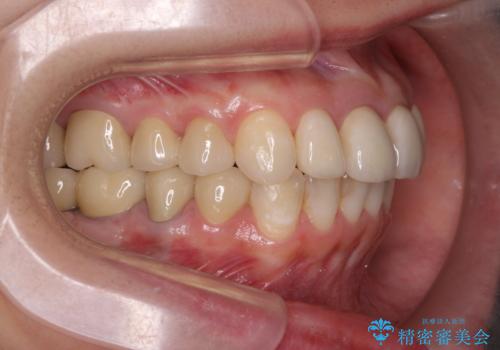

インプラント・セラミック・矯正治療を含む包括歯科診療

- 20代女性

- 矯正装置

- インビザライン

- 治療期間

- 3年

- 治療回数

- 30回以上

- 「地元の歯医者にずっと通っているが、どんどん歯が悪くなる。時間とお金がかかってもいいので徹底的に歯を治したい。」

、と総合的な歯科治療を希望されて来院されました。

虫歯や咬合関係・歯槽骨の吸収・根尖病変・歯の欠損・複合的な問題を一つずつ解決し、

安定した噛み合わせの構築・歯ブラシのしやすい環境の整備・歯内歯周の感染除去・造骨を伴うインプラント治療

を行い、長期的な予後を見込める口腔内環境を確立、整備して行きます。

- 440万円費用は治療当時の料金となります